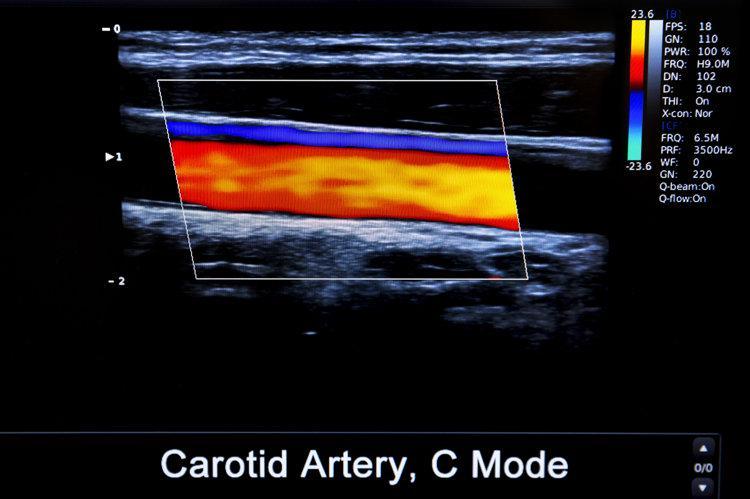

颈动脉斑块是由脂肪、胆固醇、钙质以及细胞残骸等物质组成的“杂质”,沉积在颈动脉壁上就形成了斑块,这就好比家里的水管使用久了产生的水垢。

在颈动脉斑块产生后,一般不会给身体带来异常症状。但随着斑块不断变大会影响流向大脑的血液,从而引起头晕、乏力等症状出现,严重的甚至会诱发中风、心血管疾病。